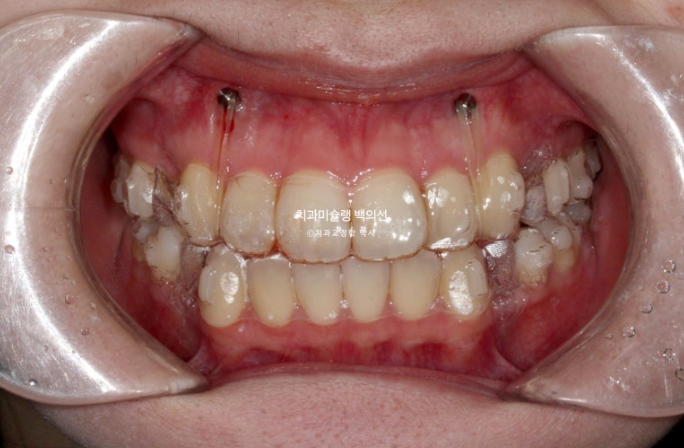

거미스마일도 심한 편이었으며 돌출과 거미스마일 해소를 위해 작은어금니 4개를 발치하고 치료에 들어갔습니다.

치료방법은 인비절라인 선택하셨고 첫 세트 장치는 85개가 나왔습니다.

23.12

일주일에 장치를 1개씩 교체해가며 치료를 진행합니다.

발치교정에서 거미스마일 개선을 위해서는 교정용 나사에 환자분이 뺏다꼈다 하는 고무줄 처방이 함께 들어갑니다.

환자분은 장치와 고무줄을 열심히 껴주었습니다.